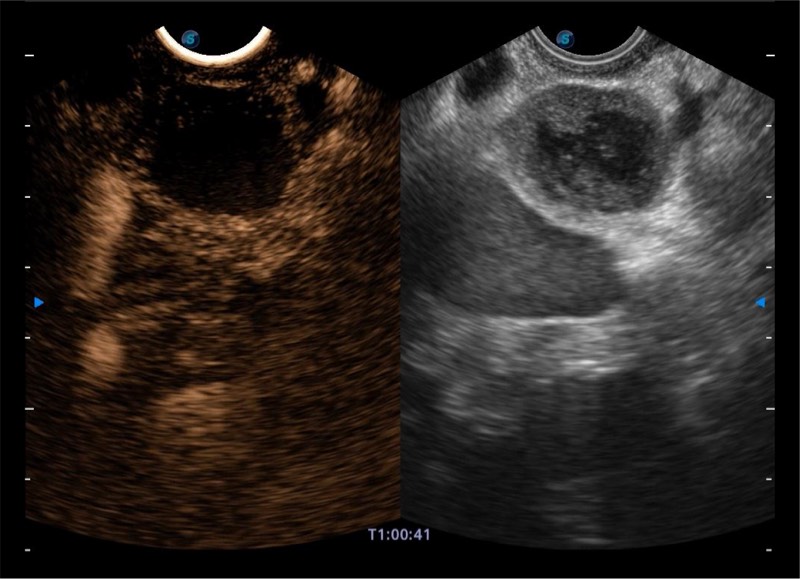

基于二十年的超声技术积累,美狮贵宾会官网提供了最新一代的独立超声主机,在提供高质量图像的同时满足多学科使用。具备常见多普勒技术并提供弹性成像、声学造影等高端影像技术。新一代传感器具有更强的抗干扰能力并减少图像伪影。